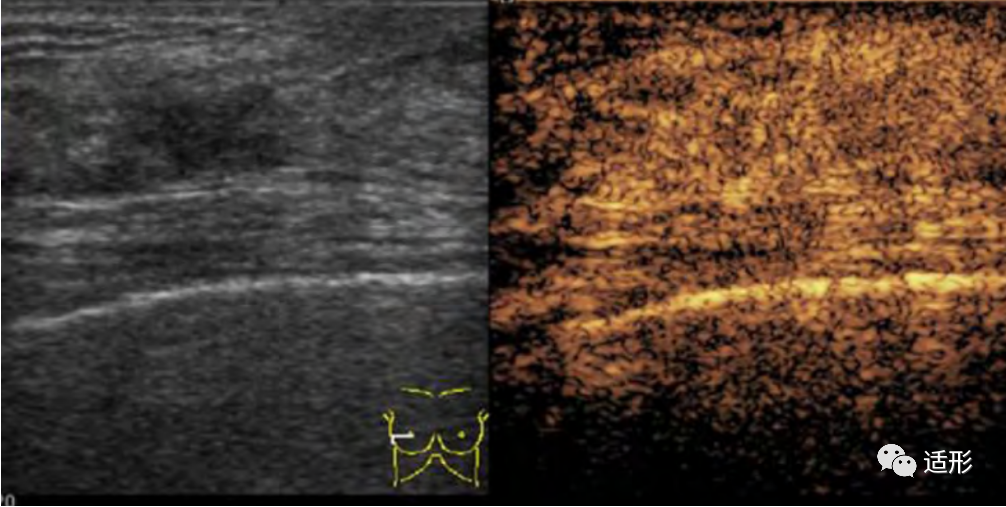

NML的弹性表现与病变的病理类型有关。恶性NML的病变硬度高于良性NML。根据病变应变式弹性成像(SE)的弹性图像表现,可利用5分评分法来评价NML的良恶性。良性NML病变较恶性NML病变软,评分多为1-3分(图1)。恶性NML较良性NML病变硬,评分多为4-5分(图2) 。结合常规超声与5分评分法评价NML,诊断恶性NML的准确性可达83.1%。另外,也可应用病变组织与皮下脂肪组织的弹性应变率比值来鉴别NML良恶性。Qu等以4.07为应变率比值截断值时,其诊断恶性NML的准确率可达95.5%。

图1. 44岁女性,超声提示乳腺内非肿块型病变,呈低回声。弹性评分(右侧)为2分,应变率比值为2.25. 病理:纤维囊性变